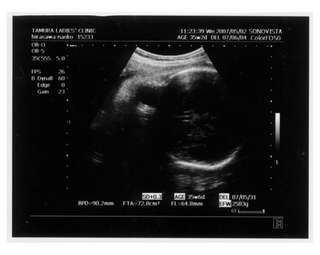

× [PR]上記の広告は3ヶ月以上新規記事投稿のないブログに表示されています。新しい記事を書く事で広告が消えます。 9ヶ月(32週と5日) 体重:2072g BPD(頭を上から見た耳から耳の幅のような感じ):84.6㎜ FTA(お腹の断面):60.8平方㎝ FL(大腿骨長 太ももの骨の長さ):61.2㎜ 9ヶ月(35週と2日) 体重:2583g BPD(頭を上から見た耳から耳の幅のような感じ):90.2㎜ FTA(お腹の断面):72.8平方㎝ FL(大腿骨長 太ももの骨の長さ):64.8㎜ 久しぶりの記事アップです ![]() なんだかあっという間にGW終わってしましましたね~ ![]() きのうは雨のせいでだらけてしまって、記事書く予定ができませんでした ![]() ダンナっちには『雨降って ナオコ 動かず』といわれています・・・ ![]() さてさて、5月2日(35週と2日)の内診では、 子宮口が1センチ開いてきてることが発覚 先生に「もう少し入れておいてよ 張ったら休まなきゃダメ」と言われ、 薬 まで出されました。子宮の筋緊張状態をやわらげて、早産を防止 するんだそうです。 「慣れるまでは心臓がドキドキしたり、 手が震えたりしますけど、大丈夫ですから」 と先生から説明を受けて、家で飲んでみると、 ほんとにドキドキ して、手もピクピク してきて、なんかラリった妊婦状態で不思議でした。 今週に入って、だいぶ慣れたようでそんなにラリっては いないけど、飲んでから1時間くらいは運転を控えています ![]() ベイビー自体は2500gをすでに超えて、動きも活発で元気にしています ![]() 1センチ開いてもなかなか進まないこともあるし、どうなるかはわかりません ![]() でも、ベイビーがお腹から出てきて自分で呼吸をするために、 必要な肺のサーファクタント(界面活性物質)の分泌は、妊娠33~36週ころから になります。 哺乳反射といって、ベイビーがおっぱいを飲むための反射的に吸い付く能力は 32~34週で完成するそうです。 網膜の血管が完成するのは35週前後だそうです。 つまり、わたしは今週臨月(36週)に入りましたが、 やっぱり正期産である37週からの出産が望ましいみたいです ![]() ![]() 医療も発達してきてるし、 ほぼ完成しているので生きられないことはぜんぜん無いんですけど、 十分に成長して「時」が満ちて生まれるのが一番みたいですね~ ![]() 「はやく会いたいけど、あと3週間くらいお腹の中にいてね~」 とベイビーに言っています ![]() 薬をもらってから、「張り」を意識するようになったんですけど、 けっこう張るんですよね~ 張るとなんとも動きづらい ![]() パンパンで重みのある厚手のゴムボール を持って歩くような・・・そして、 膀胱圧迫![]() ![]() ![]() トイレ行くにも駆け込む動作がつらい 歩けない![]() 、走れない![]() ![]() 悲惨な結末 ![]() ![]() ![]() ![]() を迎えまいとして、キュッと閉める運動をせざるをえなくなります・・・ ![]() PR この記事にコメントする